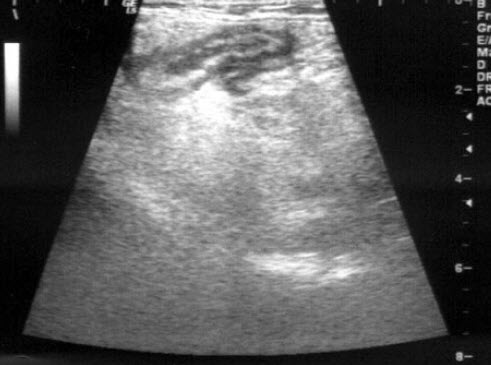

男,6岁,阵发性腹痛,呕吐数小时就诊。PE:肠鸣音亢进,呈气过水音。根据超声声像图诊断为()

A.急性肠梗阻